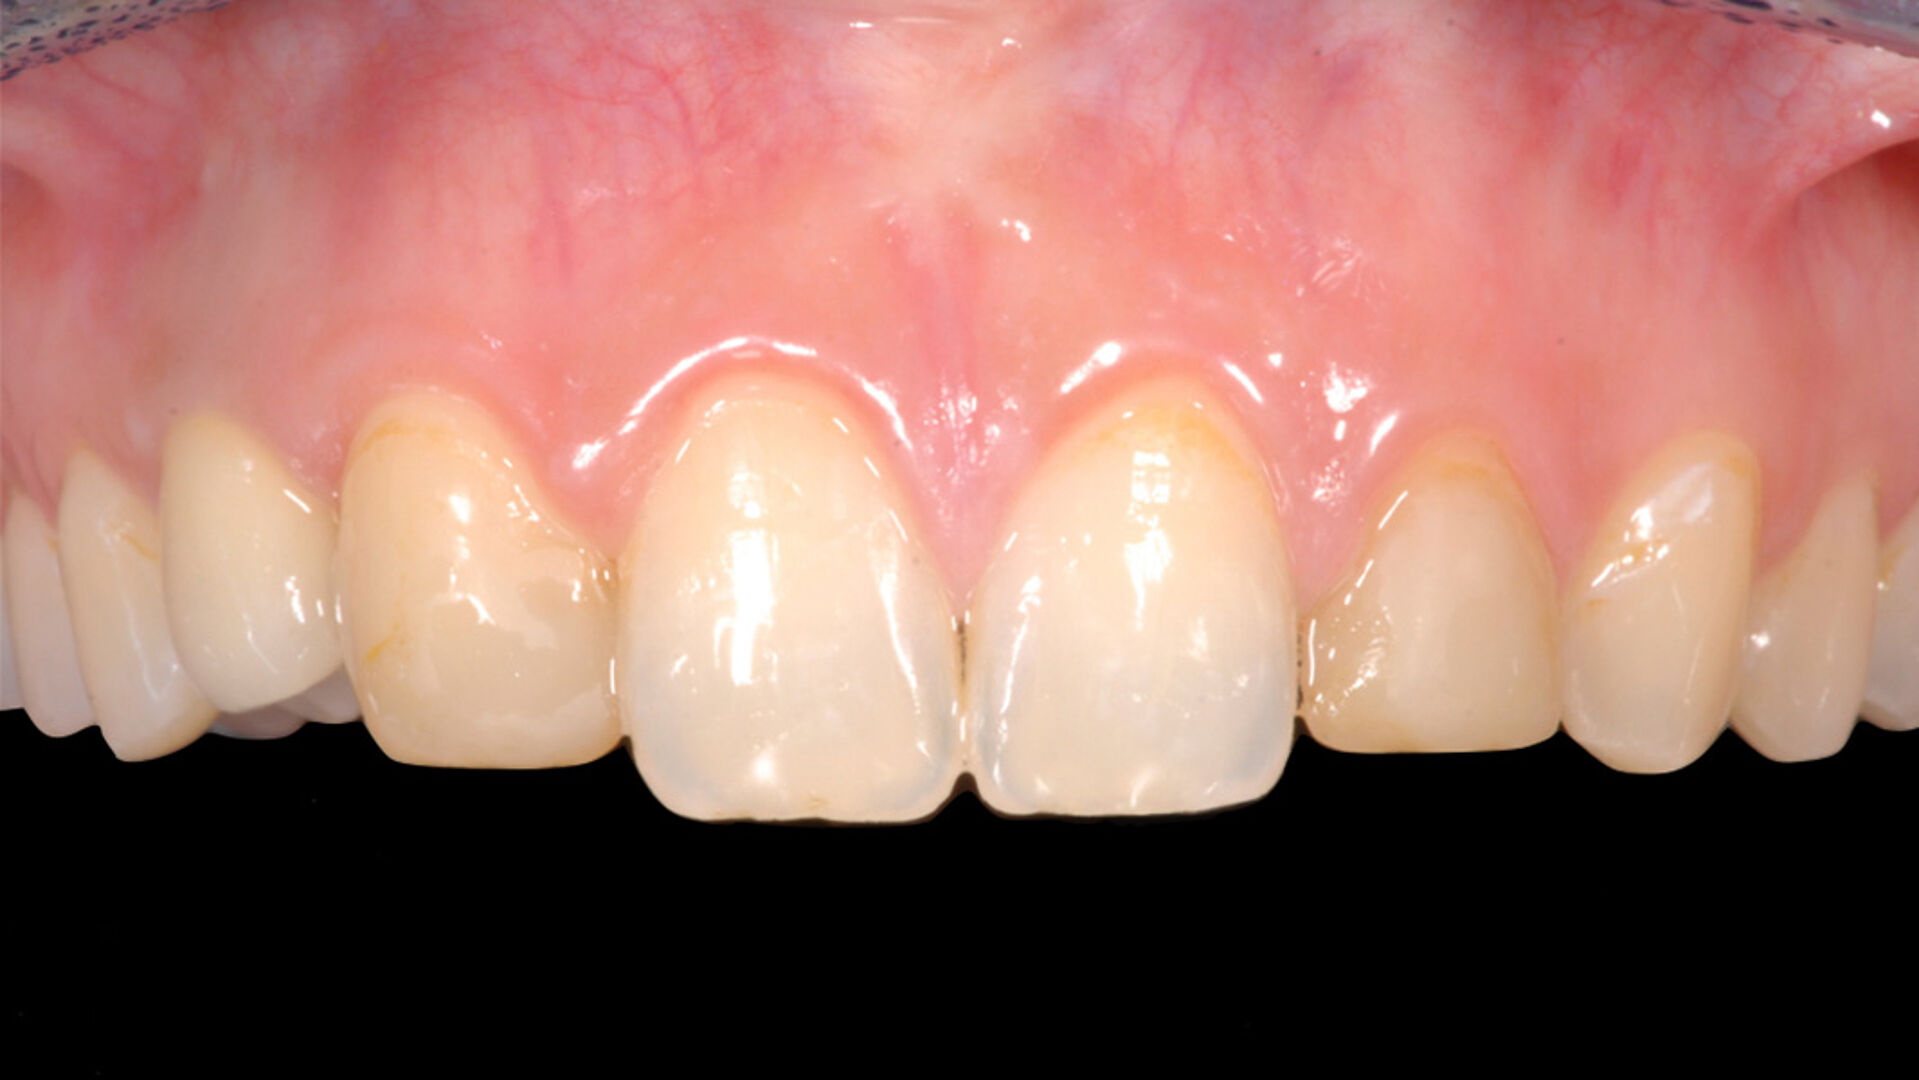

Die transgingivale Einheilung dentaler Implantate ist ein wissenschaftlich gut untersuchtes und klinisch erfolgreiches Verfahren. Für die transgingivale Einheilung sollten die Implantate primärstabil inseriert werden, nur kleine Hartgewebeaugmentationen notwendig sein und ausreichend stabiles Weichgewebe vorliegen. Um in Fällen mit Augmentationsbedarf das iSy Implantatsystem verwenden zu können – ohne die Implantatbasis demontieren zu müssen – bietet das iSy System Implantate mit gestecktem Einbringpfosten an. Nach gedeckter Einheilung und Freilegung des Implantats können drei verschieden breite Gingivaformer eingebracht und im Anschluss sowohl eine digitale als auch konventionelle Abformung durchgeführt werden. Die entsprechenden Abformpfosten und Esthomic Abutments gibt es ebenfalls in drei verschiedenen Emergenzprofilen, welche formkongruent zu den Gingivaformern sind. Im folgenden Fall wurde ein geringes bukkales Knochendefizit mit einem Gemisch aus Eigenknochen und PRF (Plättchenreiches Fibrin) augmentiert und das Weichgewebedefizit mit einer azellulären dermalen Matrix (NovoMatrix/ BioHorizons) aufgebaut.

Nicht nur die korrekte dreidimensionale Positionierung der Implantate, sondern auch das Know-how der Knochenaugmentation und die entsprechende Manipulation des Weichgewebes sind essenziell für den Erfolg. Die Kieferknochenrekonstruktion mit autologen Knochenblöcken, die nach der Beschreibung von Prof. Dr. F. Khoury ausgedünnt werden, sowie das Auffüllen der entstandenen Hohlräume mit autologen Knochenspänen führen zu einem vorhersagbaren, langzeitstabilen laminären Knochen. Auch das Implantatdesign mit der parallelwandigen Schulter sowie das Platform-Switching tragen maßgeblich zur erfolgreichen Rekonstruktion bei. Ein weiterer Vorteil des iSy Implantatkonzepts ist die Implantatbasis. Bei transgingivaler Einheilung verbleibt sie bis zur endgültigen Versorgung auf dem Implantat. Die Manipulation des Weichgewebes durch häufigen Abutmentwechsel hat laut Studien einen beachtlichen Anteil an Knochen- und Weichgewebsveränderungen. Auch bei gedeckter Einheilung werden ab dem Zeitpunkt der Freilegung mithilfe der Implantatbasis Abutmentwechsel minimiert.